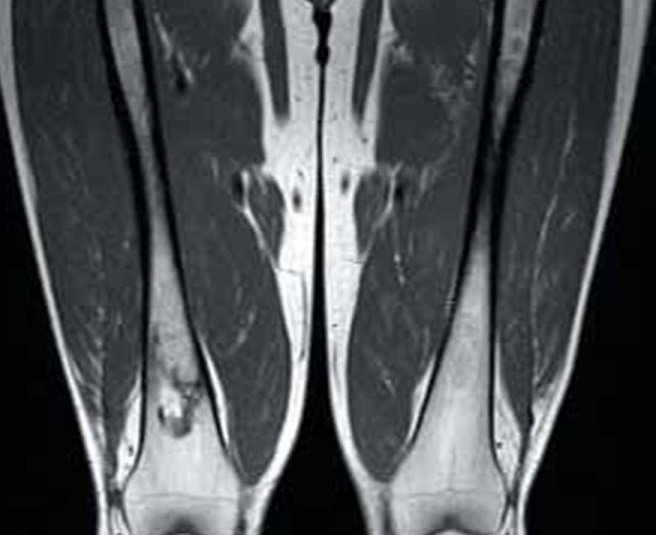

La maladie de Gaucher de type 1 (MG1) est une maladie multisystémique rare due à un déficit génétique en bêta-glucocérébrosidase lysosomale. Ses signes cliniques sont très polymorphes: splénomégalie (95%), hépatomégalie (80%), cytopénies (thrombopénie, anémie, neutropénie)... L'atteinte ostéoarticulaire est une complication majeure qui se voit dans 70 à 100% des cas selon les séries. Les anomalies du remodelage osseux induisent les classiques déformations distales des fémurs ou proximales des tibias en “flacon d'Erlenmeyer”, généralement de façon bilatérale et symétrique, avec une perte de la concavité de la région métaphysaire et un élargissement anormal de l'os à cet endroit. Un Homme âgé de 20 ans qui présente une MG1 diagnostiquée à l'âge de 4 ans était hospitalisé pour des douleurs osseuses diffuses. L'examen clinique objectivait une splénomégalie énorme allant jusqu'au pelvis, une hépatomégalie modérée et une douleur exquise à la palpation des épineuses lombaires. A la biologie, il existait une thrombopénie à 97000/mm3. La radiographie standard des fémurs montrait une déformation des tiers inférieurs des fémurs donnant l'aspect d'Erlenmeyer. L'IRM des confirmait l'infiltration médullaire des deux fémurs et du bassin avec des anomalies de signal en rapport avec des infarctus osseux.